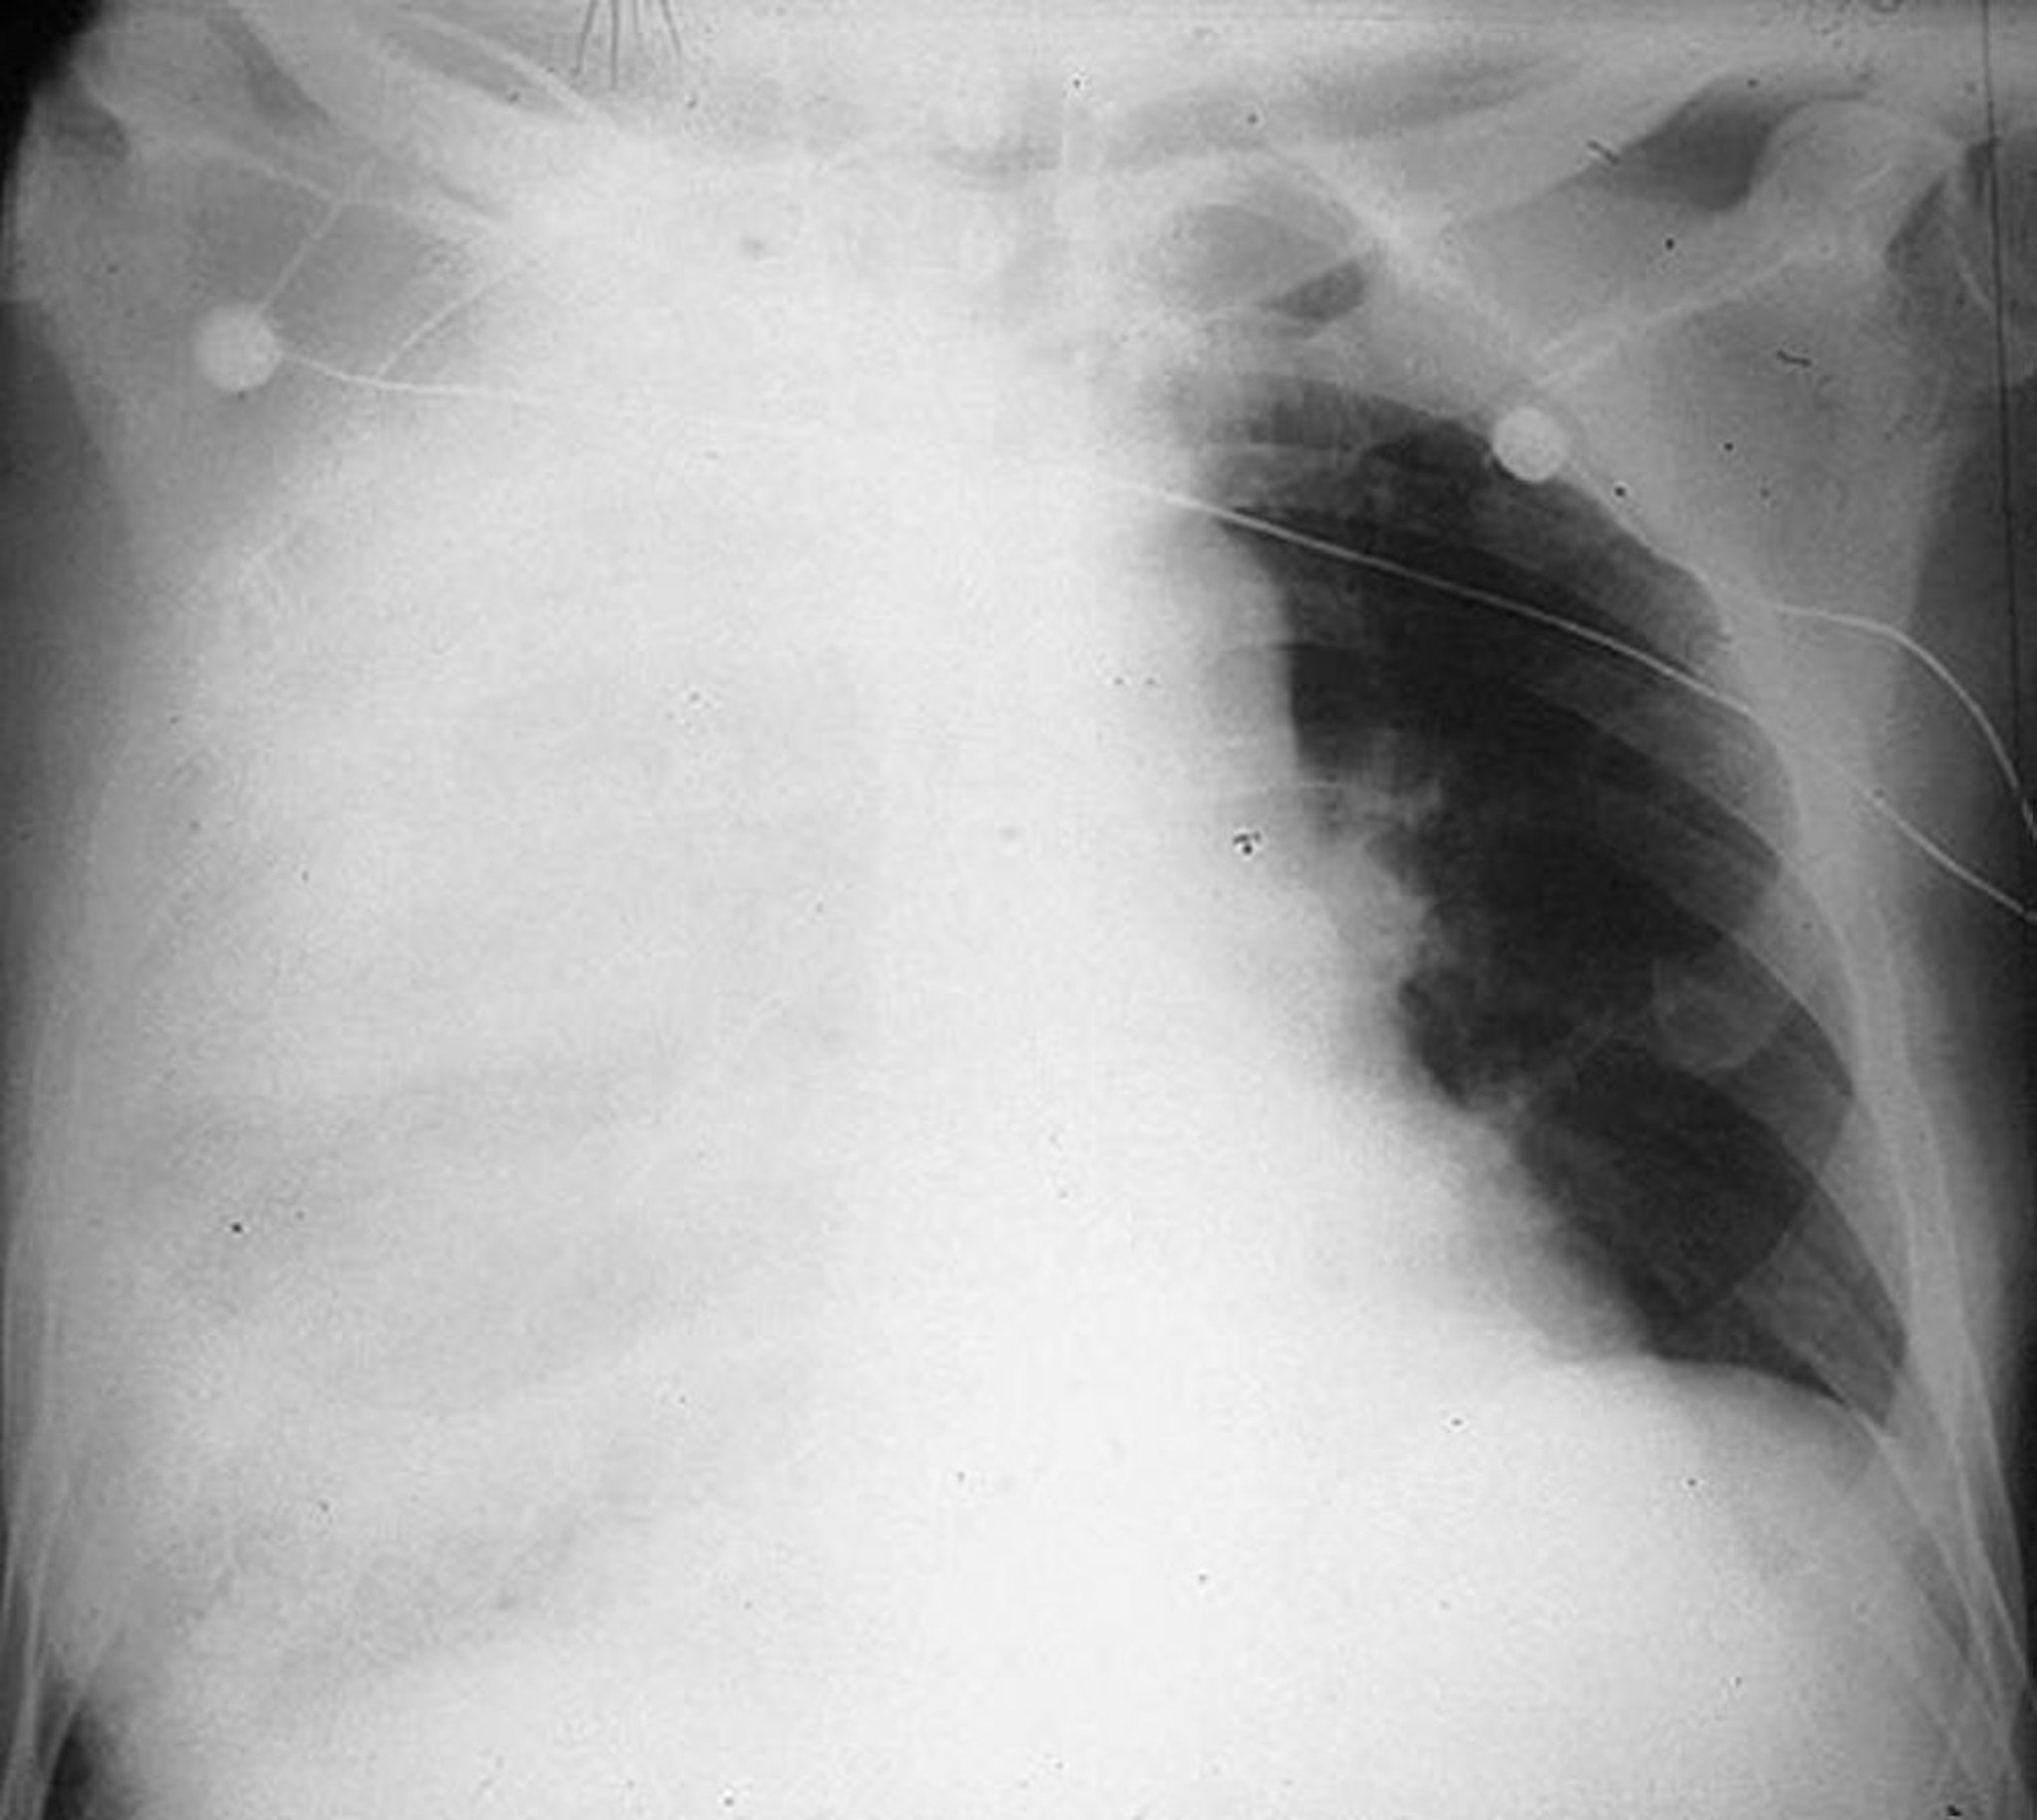

Pneumonie multilobaire

Consolidation des lobes supérieurs, moyens et inférieurs droits chez un homme de 64 ans atteint de pneumonie à pneumocoque.